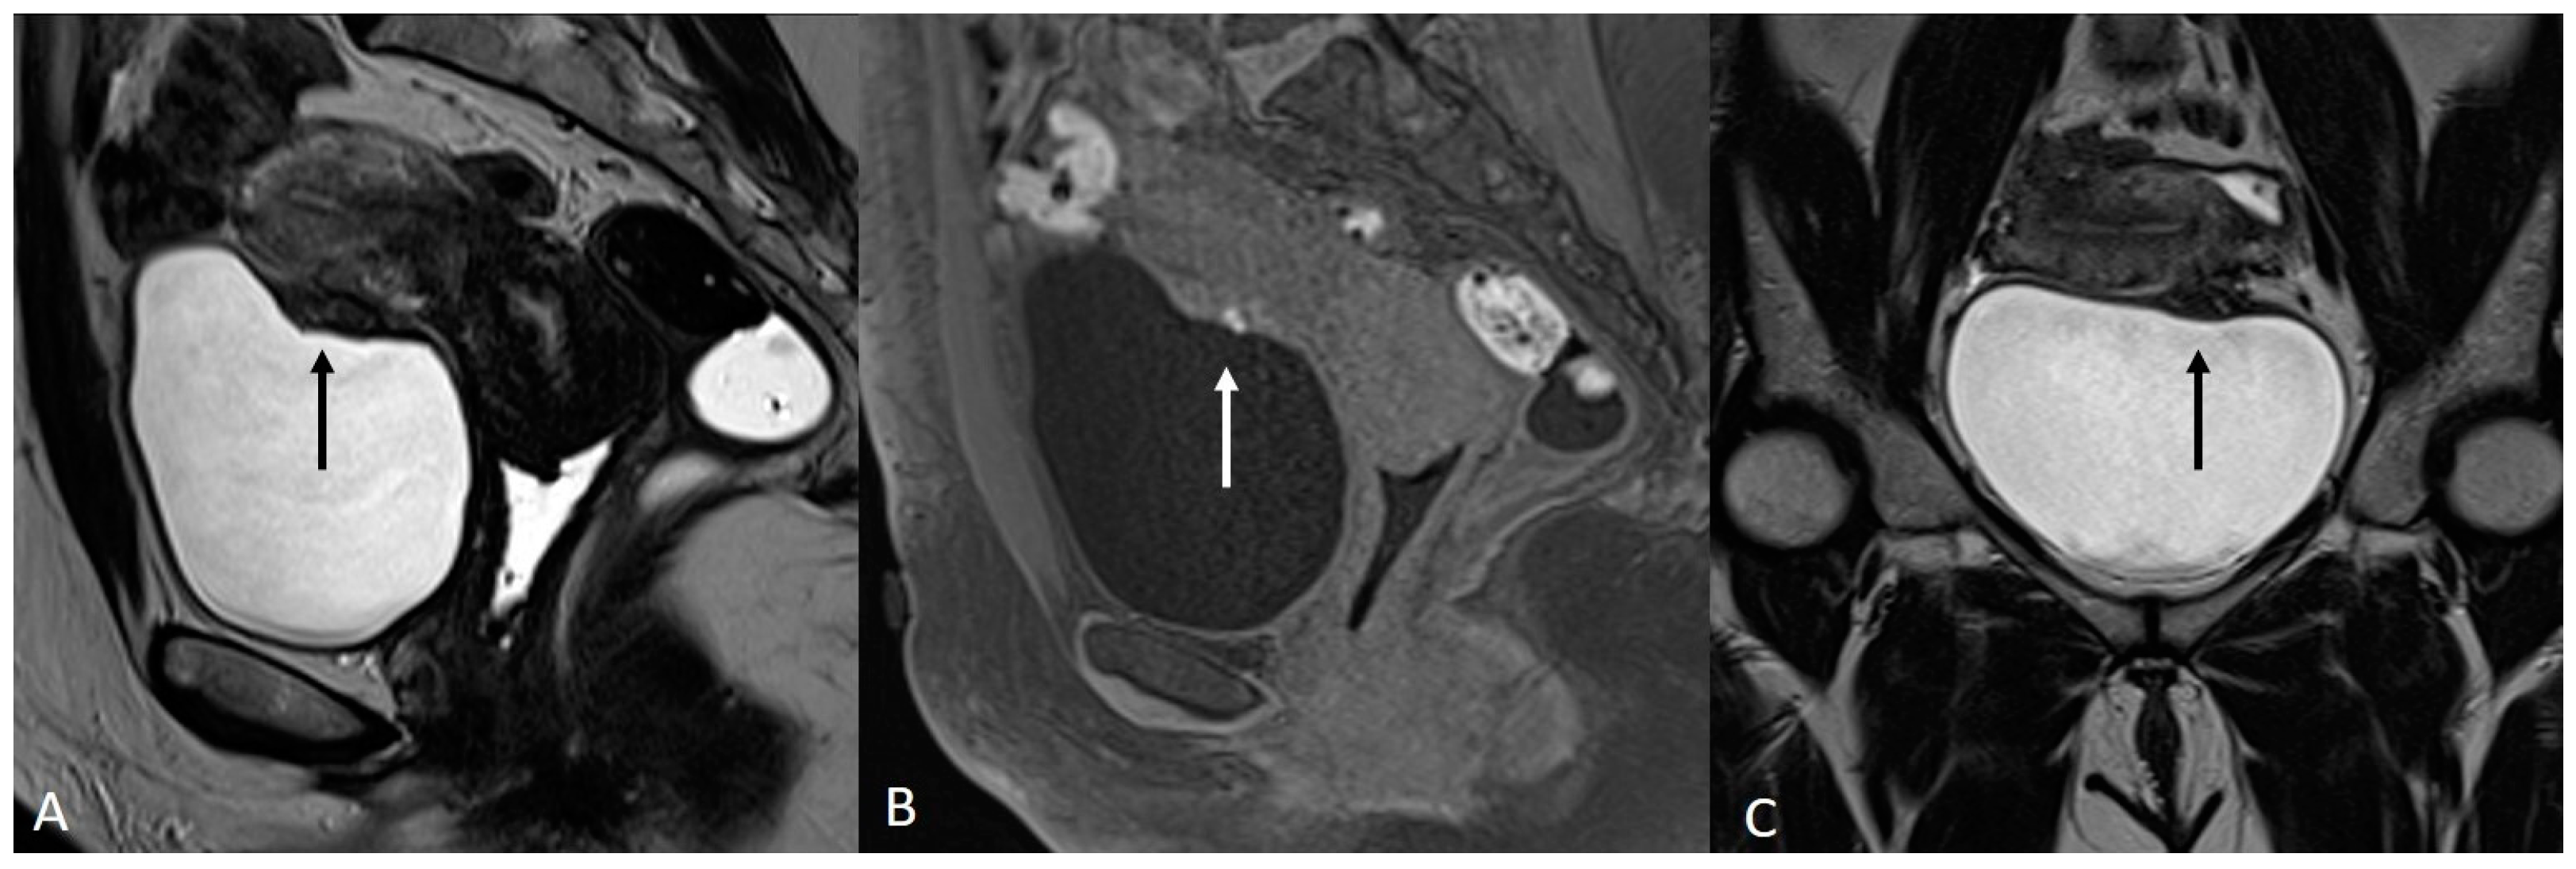

In order to perform a correct evaluation, the bladder must be at a degree of repletion suitable for the correct study of its walls and its lumen: those nodules or masses are responsible for the loss of the normal hypointense signal of the muscularis layer on T2WI. Hemorrhagic content may also be seen as hyperintense foci on T1WI, and it is also possible to observe hyperintense cystic areas on T2WI [7,14] (Figure 1).

Figure 1.

Localization of endometriosis in the vesico-uterine pouch in a 42-year-old female. (A) Sagittal T2WI (black arrow); (B) Sagittal fat-suppressed T1WI (white arrow); (C) Coronal T2WI (black arrow).

In the case of a mural mass protruding into the lumen, mucosal or submucosal edema is well depicted on T2WI [40].